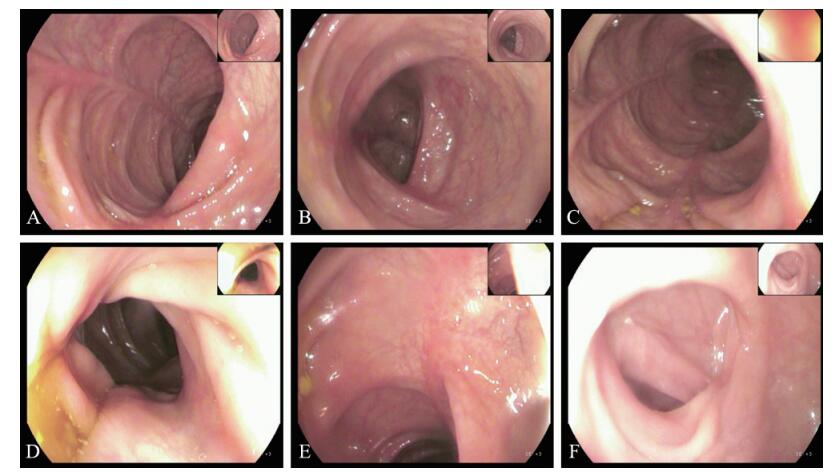

入院后嘱患者禁饮食,给予抑酸、止血、抗感染、营养支持等对症治疗。患者疼痛反复出现,剧烈难忍,间断给予山莨菪碱、布桂嗪注射液后症状无缓解,于2018年1月8日行胃镜检查示慢性萎缩性胃炎。磁控胶囊内镜检查示回肠黏膜多发点状糜烂,黏膜充血水肿。结肠镜示全结肠黏膜多发片状糜烂、溃疡,表面覆有黄苔,黏膜广泛充血水肿,血管纹理模糊,以横结肠、降结肠、乙状结肠明显(图 3)。黏膜组织病理检查示升结肠、横结肠、降结肠黏膜组织内可见灶状出血,小血管周围见中性粒细胞、嗜酸性粒细胞浸润,局灶区表面可见坏死(图 4)。结合症状、体征及辅助检查,确诊为腹型过敏性紫癜,立即给予口服泼尼松30 mg/d、非索非那定120 mg/d抗炎、抗过敏治疗,糖皮质激素治疗2周后减量5 mg/周,逐周递减。随访1个月复查肠镜,肠黏膜完全愈合,肠镜示升结肠、横结肠、降结肠黏膜可见散在条索状隆起,黏膜潮红,血管纹理清晰,无水肿、糜烂及溃疡、出血,乙状结肠、直肠上段黏膜光滑(图 5)。

图 3 一例腹型过敏性紫癜患者治疗前结肠镜检查 A、B:升结肠; C~E:横结肠; F:降结肠 |